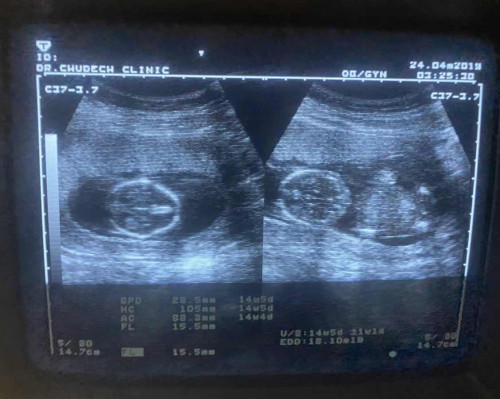

ไปหาหมอมา 14w 5 d หมอบอกว่าน่าจะผู้ชาย แต่ยังไม่ค่อยแน่ใจ รบกวนแม่ๆช่วยดูทีจ้า ว่า ญ รึ ช ลุ้นมากเลยค่ะ